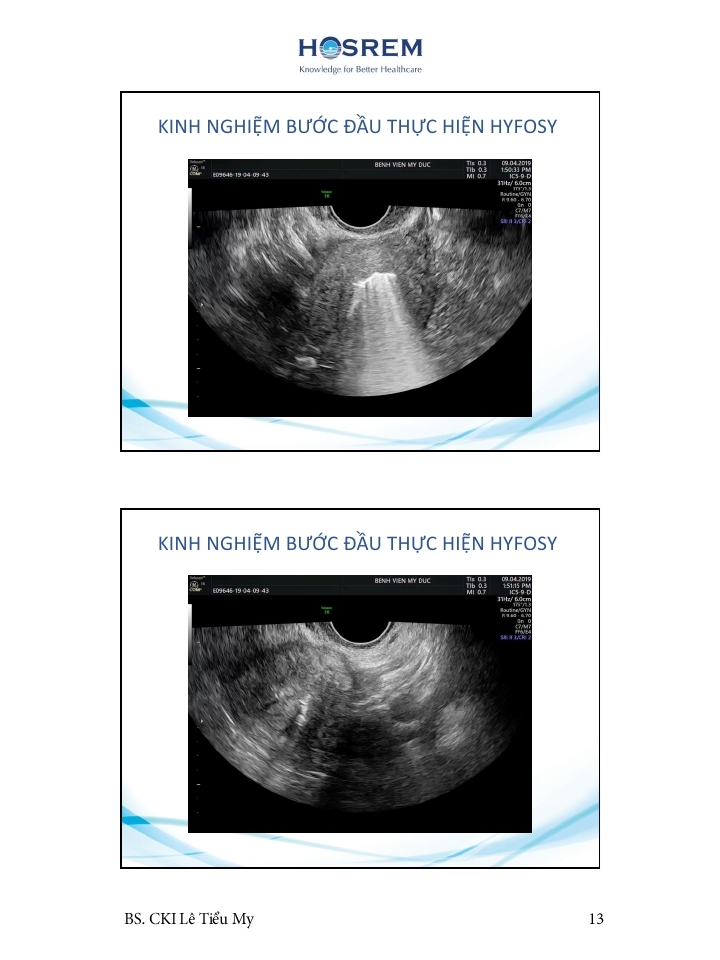

Các phương pháp đánh giá ống dẫn trứng